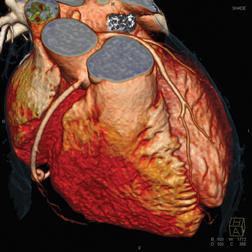

The push for healthcare to be digitally transformed and paper-free means having access to electronic medical records anytime/anywhere. This effort amplified, has left many cardiology departments struggling to catch up. According to the Administration on Aging people 65+ represented 12.4 percent of the population in the year 2000, but are expected to grow to be 19 percent of the population by 2030. The increase in longevity-on top of advances in medications, less invasive treatments and diagnostic testing will greatly increase demand for cardiology.